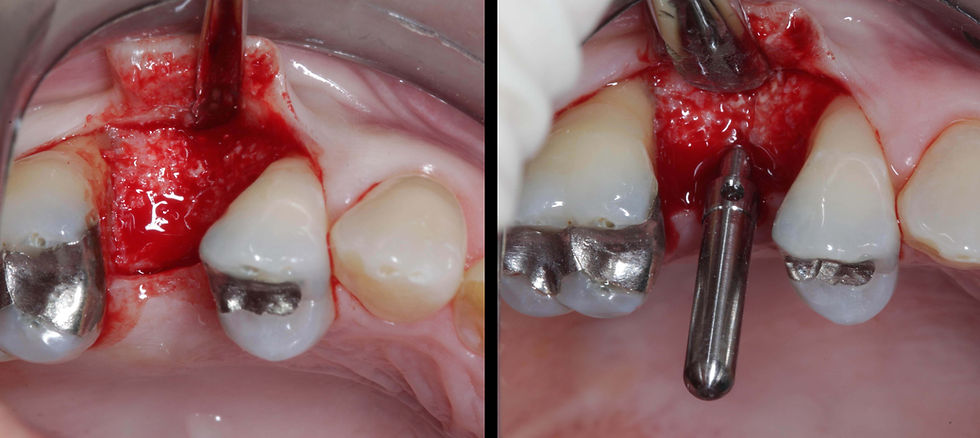

Second surgical step: the flap is open, observing that the bone volumes are regenerated. A parallelism pin is inserted after surgical site preparation, to verify the implant insertion axis.

Prama implant in place and insertion of a surgical cover screw. The surgery is completed with a tension-free secondary wound closure with PTFE sutures; removed after 2 weeks.